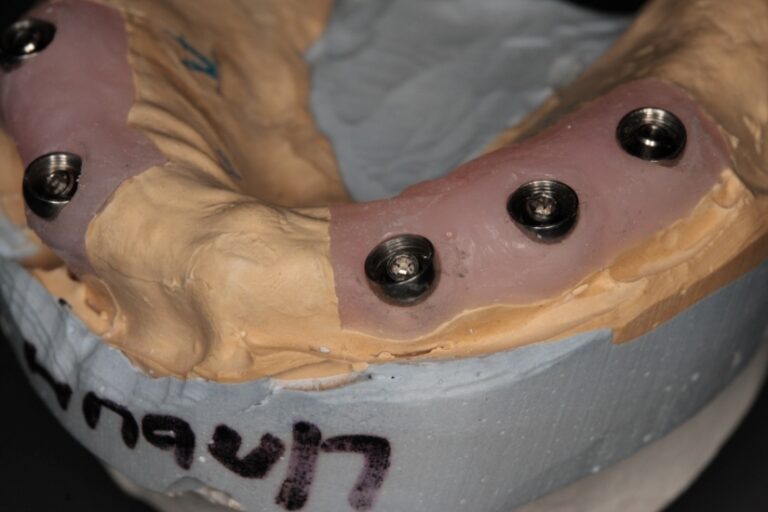

Photo 4a, b. Response component of Alpha Dent Implants Adapter in the bridge.